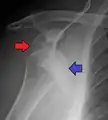

A Hill–Sachs lesion is an impaction of the head of the humerus left by the glenoid rim during dislocation.[6] Hill-Sachs deformities occur in 35–40% of anterior dislocations. They can be seen on a front-facing X-ray when the arm is in internal rotation.[11] Bankart lesions are disruptions of the glenoid labrum with or without an avulsion of bone fragment.[12]

Anterior dislocation of the right shoulder. Y view X ray.